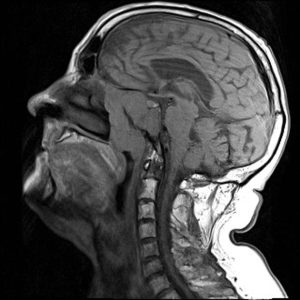

Nasopharyngeal carcinoma. Nasopharyngeal carcinoma, another name for nasopharyngeal cancer (NPC), is an uncommon form of head and neck cancer. The tissue that joins the rear of your mouth to the back of your nose is impacted. This region, known as the nasopharynx, is situated at the base of your skull, directly above the roof of your mouth. Air enters your body through your nose, passes through the nasopharynx, and then enters your throat before entering your lungs.

However, the nasopharynx, the tissue that joins the back of your mouth to the back of your nose, is where nasopharyngeal carcinoma, a rare kind of cancer, begins. Although the most typical sign is a painless lump on the back of your neck, it can also impact your ears, leading to persistent ear infections or hearing loss. Additionally, it may result in numbness and face pain. The stage of the cancer determines the specific treatment.